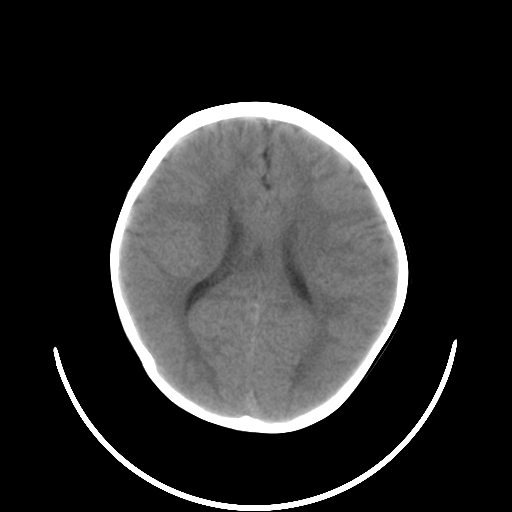

以下是引用拾荒者在2009-10-17 18:38:00的发言:[br]鼻面部皮下积气,右侧睑缘及眼球壁高密度异物影,左侧眼球壁晶状体内侧缘处是圆形低密度影。低密度异物?应提请眼科医生注意。